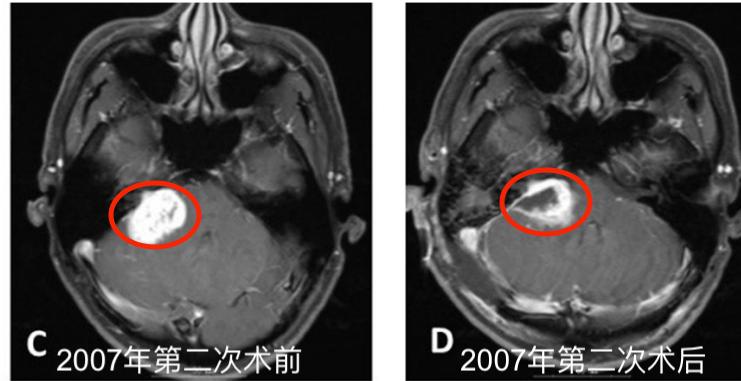

C. 2007年5月第二次切除术前轴位钆剂(Gd)增强T1加权MR图像。D.第二次切除术后1个月轴位钆剂(Gd)增强T1加权MR图像。

2004年5月,采取右侧乙状窦后入路切除肿瘤。术中肿瘤质地坚实(solid),血管相对丰富,易出血,部分切除肿瘤(图1A-B),于2005年8月行伽玛刀放射外科治疗(GKS)(图2)以控制当时的残留肿留。2007年5月行第二次手术切除,因蛛网膜边缘不清,与面听神经和后组颅神经粘连严重,残留部分肿瘤囊壁(图1C-D)。病人每6个月定期随访脑部MRI(图1E-I),最初的残留肿瘤的大小是稳定的。2013年11月,常规随访MRI显示肿瘤开始生长(图1J)。2014年4月出现进行性头痛、眩晕、和恶心,MRI显示肿瘤肿块增大。2014年6月(图1K-L)进行次全肿瘤切除,术中发现显示,肿瘤有两个部分,也就是说,有一部分是软的且相对容易切除,另一部分有弹性伴有纤维组织,蛛网膜边界不清楚,与面听神经和后组颅神经严重粘连。本病例的第二次及第三次手术均由同一位神经外科医生完成。